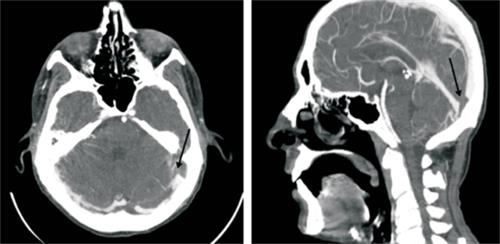

b) en cabeza y cuello: trombosis de la vena yugular izquierda que compromete afluente facial a nivel de cuello con extensión a nivel cefálico hasta seno sigmoideo y transverso izquierdos, ocupación parcial del oído medio izquierdo con ocupación total de celdillas mastoideas, y

c) abdomen: sin alteraciones (figura 2), (figura 3) y (figura 4).

Figura 3: Angiotomografía de vasos de cuello. Se observa defecto de relleno en toda la extensión de la vena yugular interna izquierda.